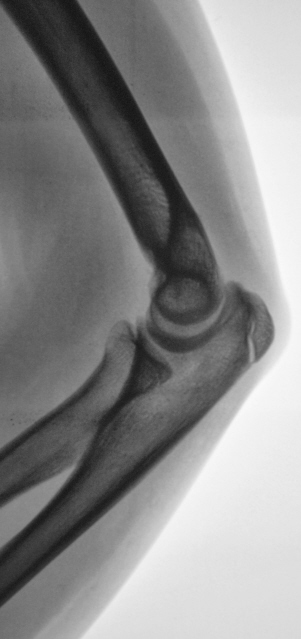

Малышка – Иринка, правоту которой я предполагаю, предположила апофизеолиз локтевого отростка, а его, на мой взгляд, можно определить лишь в боковой проекции.

Конечно, Петрович - Вы правы. Формально можно предположить апофизеолиз локтевого отростка, с учетом неравномерности ширины "зоны росткового хряща". Но из-за болевого синдрома, классическую "строго боковую" лаборантам произвести не удалось.

А апофизеолиза локтевоо отростка здесь нет? Зона роста неравномерная, резко сужена в верхнем отделе.

На здоровой руке обычная зона роста, на травмированной зона роста очень расширена. Это эпифизеолиз.

Нет, апофизеолиза локтевого отростка здесь нет.

Здесь не хватает боковой проекции здоровой руки. Больная же в боковой проекции снята вполне удовлетворительно.